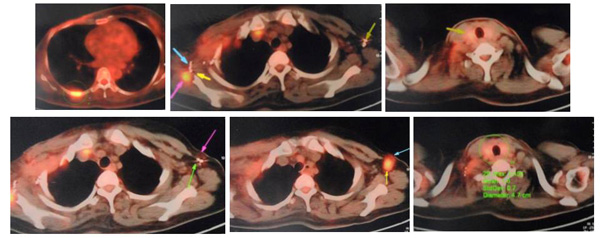

In June to August 2011, KT went to China for treatment. PET/CT scan showed the wound was 14 x 12 cm and the cancer had spread to her lymph nodes, lungs and bone. This was a Stage 4 cancer.

- Patient received iodine seeds implantation and cryosurgery in the lung,

- Iodine seeds implantation in the axillary fossa metastatic lymph nodes.

27 September 2011: Patient received iodine seeds implantation in the scapular region and left costal bone.